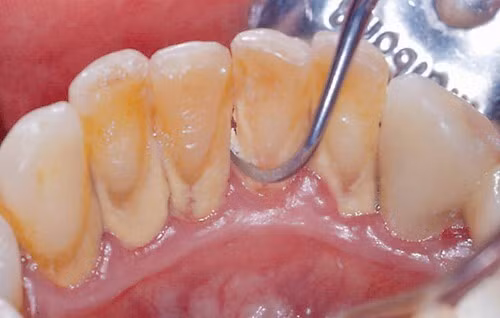

Nguyên nhân phổ biến nhất của viêm lợi là sự tích tụ của mảng bám vi khuẩn giữa và xung quanh răng. Các mảng bám kích hoạt phản ứng miễn dịch, do đó, có thể dẫn đến phá hủy nướu hoặc mô nướu. Cuối cùng, nó sẽ dẫn đến các biến chứng khác.

Mảng bám răng là một màng sinh học tích tụ tự nhiên trên răng. Nó thường được hình thành do vi khuẩn khu trú đang cố gắng bám vào bề mặt nhẵn của răng.

Những vi khuẩn này có thể giúp bảo vệ miệng khỏi sự xâm chiếm của các vi sinh vật có hại, nhưng mảng bám răng lại gây sâu răng và các vấn đề về nha chu như viêm nướu, nhiễm trùng nướu.

Khi mảng bám không được loại bỏ, nó có thể cứng lại thành vôi răng, hoặc cao răng, ở chân răng, gần nướu. Cao răng thường có màu vàng.

Mảng bám và cao răng cuối cùng gây kích ứng nướu, gây viêm nướu quanh chân răng, khiến nướu dễ bị chảy máu.